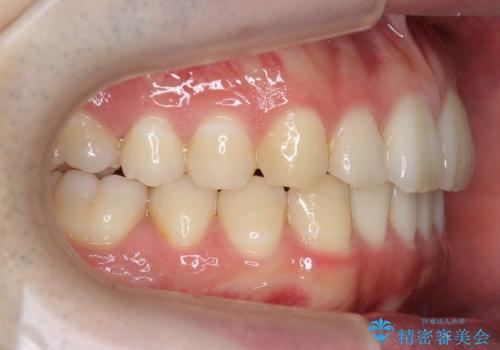

左下の奥歯を後ろに移動して、中に入ってすれちがっていた小臼歯を並べました。

他院で歯を抜かずにマウスピースで難しいといわれた方、ぜひご相談ください。

- 95万円費用は治療当時の料金となります